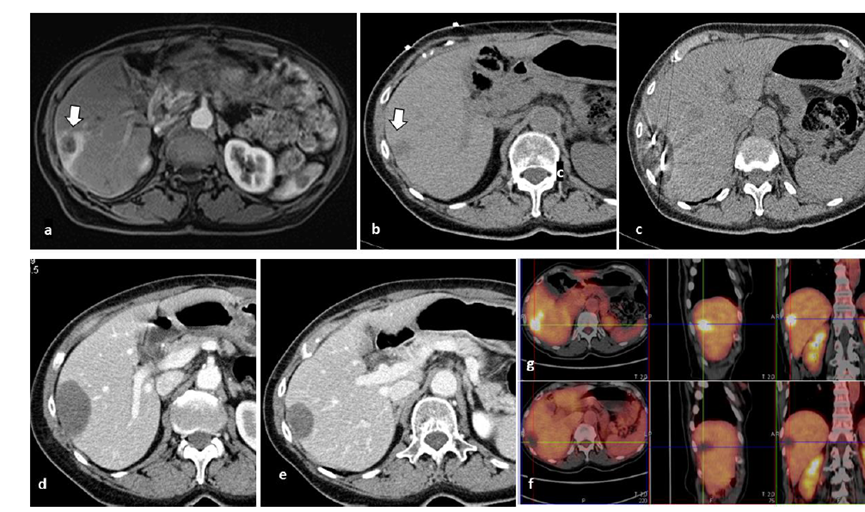

79 歲男性,肝轉(zhuǎn)移(結(jié)直腸癌)腫瘤的完全消融病例

( a ) 軸向 MRI 和 ( b ) 軸向 CT 顯示肝S8段有一個(gè)16mm的病灶,鄰近肝緣。( c )冷凍消融期間CT顯示放置了2個(gè)冷凍探針,低密度冰球包圍病灶。(d)術(shù)后1個(gè)月隨訪 CT顯示冰球?qū)?yīng)的壞死區(qū)域,未見復(fù)發(fā)。(e)術(shù)后6個(gè)月的CT,壞死區(qū)域縮小,未見復(fù)發(fā)。(f)與基線影像(g)相比,12個(gè)月后的FDG-PET/CT顯示未見FDG攝取。